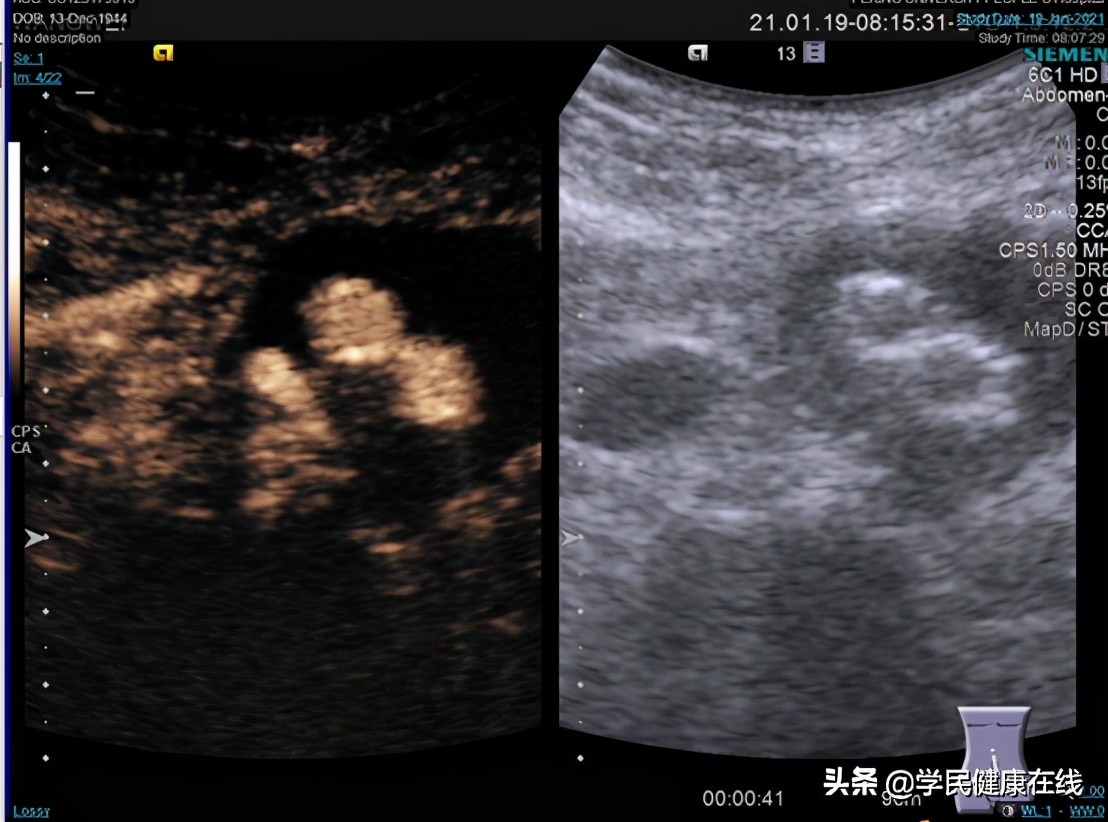

图5. 术前超声造影,可见后壁有造影剂进入

图6. 术后造影,已无明显造影剂进入瘤囊